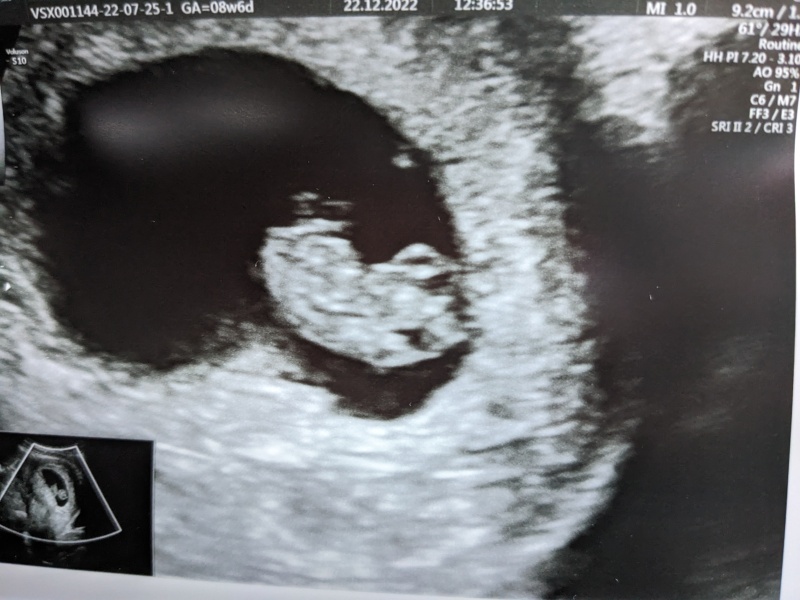

rach971 · 22/12/2022 14:44

I've just had a private scan today. 8+6 and baby was moving around and sucking its thumb ☺️

squirrelnutkins1 · 22/12/2022 15:18

Amazing!!